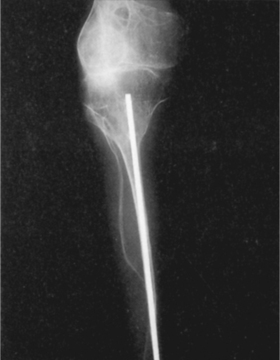

Fracture immobilization is as minimal as possible to prevent disuse atrophy. A repeated cycle of fractures-immobilization of the same bone can inhibit progress in mobility and the development of strength (Fig. 23-31). The use of intramedullary rods is one way of managing recurring fractures (Fig. 23-32). Indications for this procedure include more than two fractures in the same long bone within a 6-month period, lower extremity bone angles greater than 40 degrees, or very unstable lower extremities in a child who appears ready to walk. Telescoping intramedullary rods are used to stabilize the bones, elongating as the bone grows, although this procedure is not without risk.

Figure 23-32 Radiograph of the leg of an individual with severe clinical osteogenesis imperfecta that has been treated by rodding of the tibia. The extreme ribbonlike quality of the bones is apparent in the fibula. (From Bullough PG: Bullough and Vigorita’s orthopaedic pathology, ed 3, St Louis, 1997, Mosby, p 135.)

The reoperation rate is significant, with complications related to osteopenia that occurs around the rods (greater around thicker rods), rod migration, and bony growth even beyond the available expansion. Osteotomies also are performed to help control rotational deformities, with appropriate bracing to prolong the time period between potential surgeries.